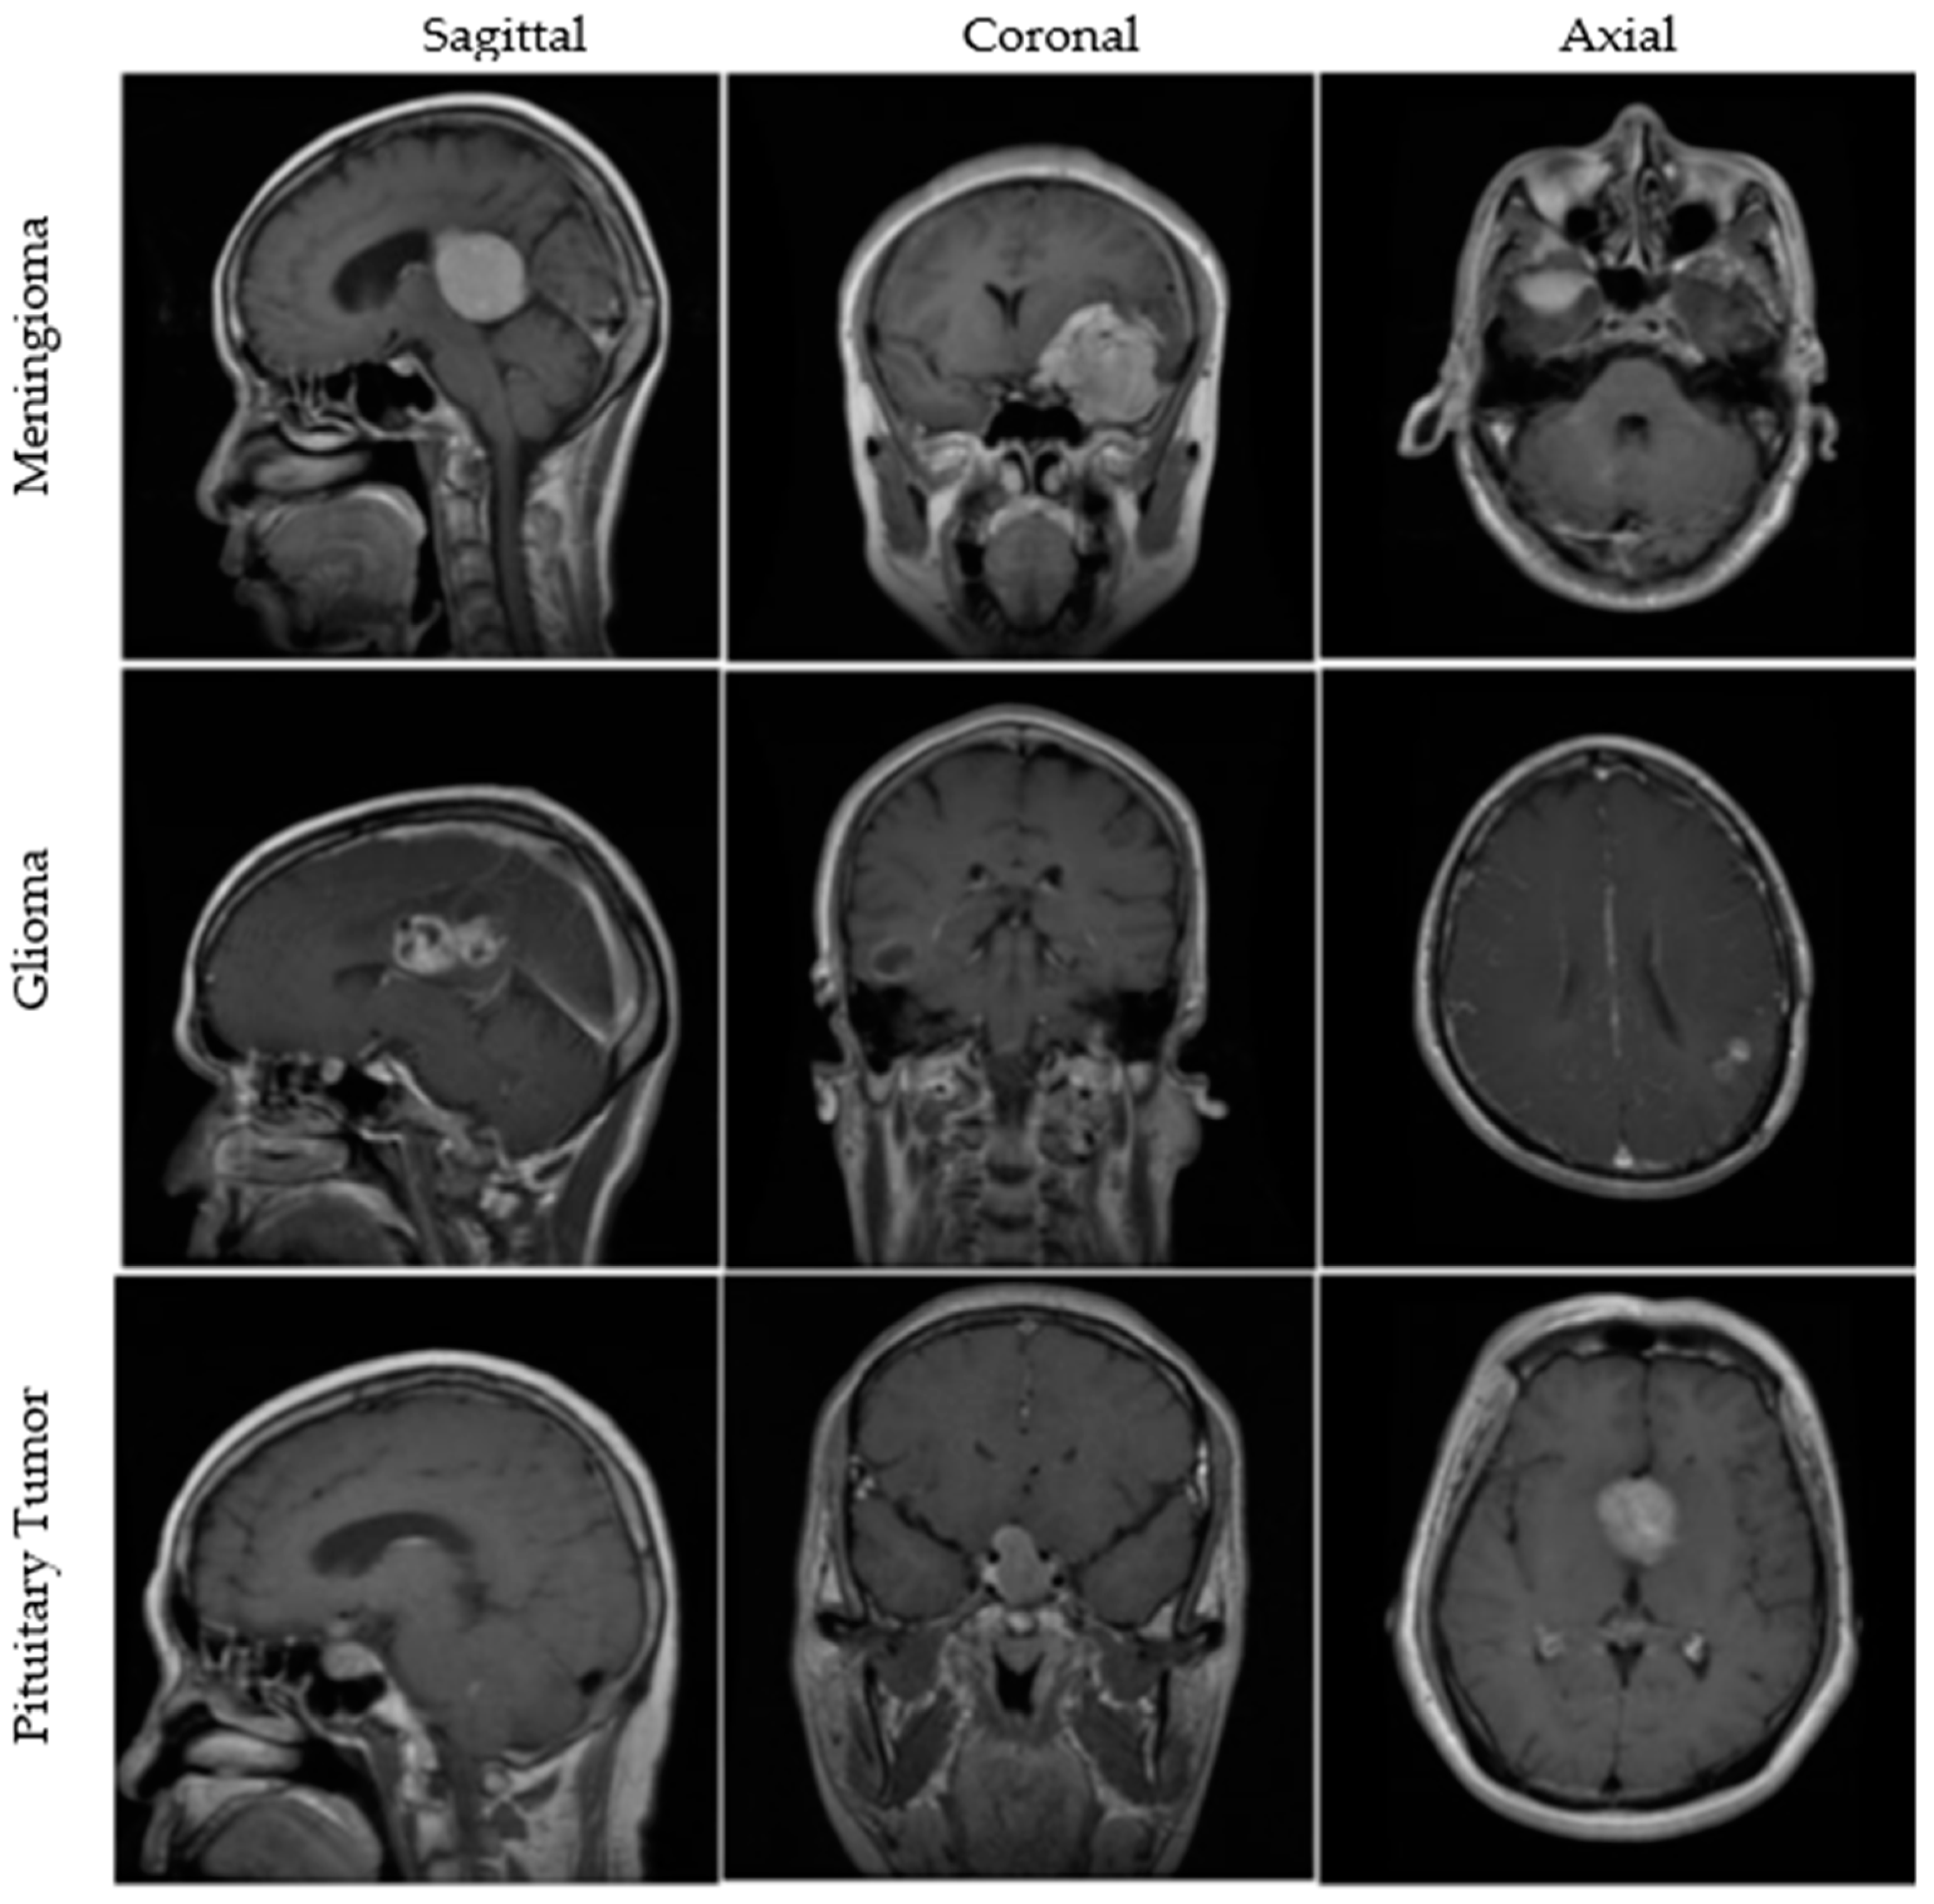

An openly available dataset from figshare consists of 3064 T1w CE MRI slices from 233 patients with meningiomas, gliomas, or pituitary tumors. The images are available in all sagittal, coronal, and axial directions, with spatial resolutions of either 512 × 512 or 256 × 256. More details about the dataset are available in [40,41]. A few MRI images from the dataset are illustrated in Figure 1. Furthermore, brief clinical descriptions about the three types of tumors are given below.

Figure 1.

MRI images from the figshare dataset are shown in sagittal, coronal, and axial cut planes for meningiomas, gliomas, and pituitary tumors.